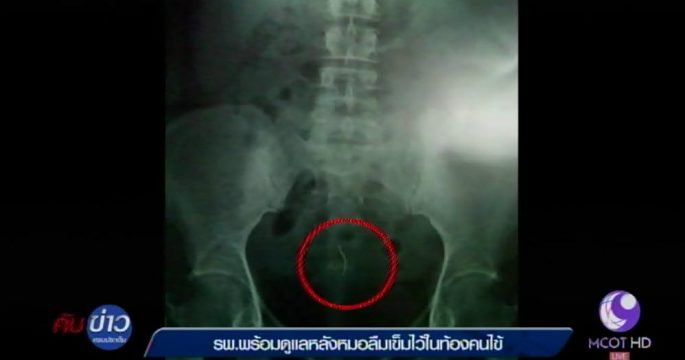

โรงพยาบาลปากช่องนานา แถลงพร้อมดูแลผู้ป่วยกรณีเอกซเรย์พบเข็มในท้องคนไข้ หลังเข้ารับการผ่าตัดคลอดบุตรเมื่อ 12 ปีก่อน